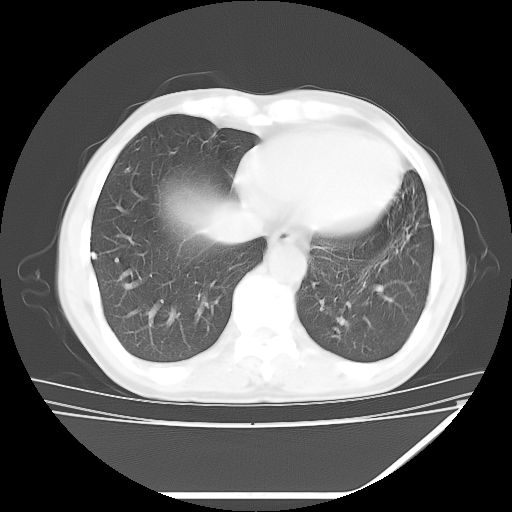

男,59岁,“结核性胸膜炎”30余年,胸部经常疼痛,多次x检查提示“肺部”炎症。腹部疼痛5日,b超提示:“肝内短管结石,余显示不清,建议进一步检查。”

两肺结核并右侧胸腔积液;脾脏、腹腔及腹膜后淋巴结结核[陈旧性];肝内胆管结石

胸部腹部都是结核(双肺。纵隔淋巴结,肝脏,脾脏,肠系膜)